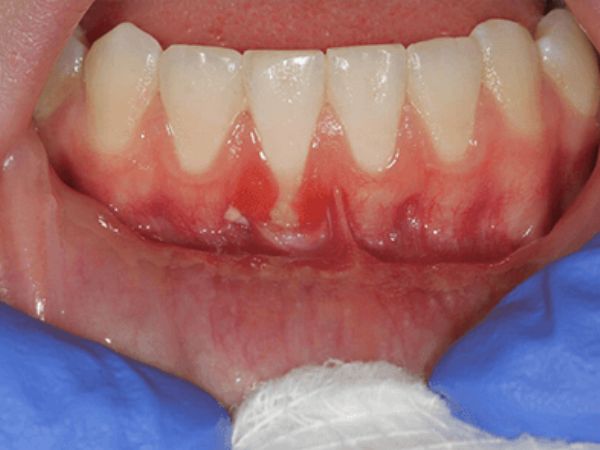

Before gum treatment Before

After gum treatment After